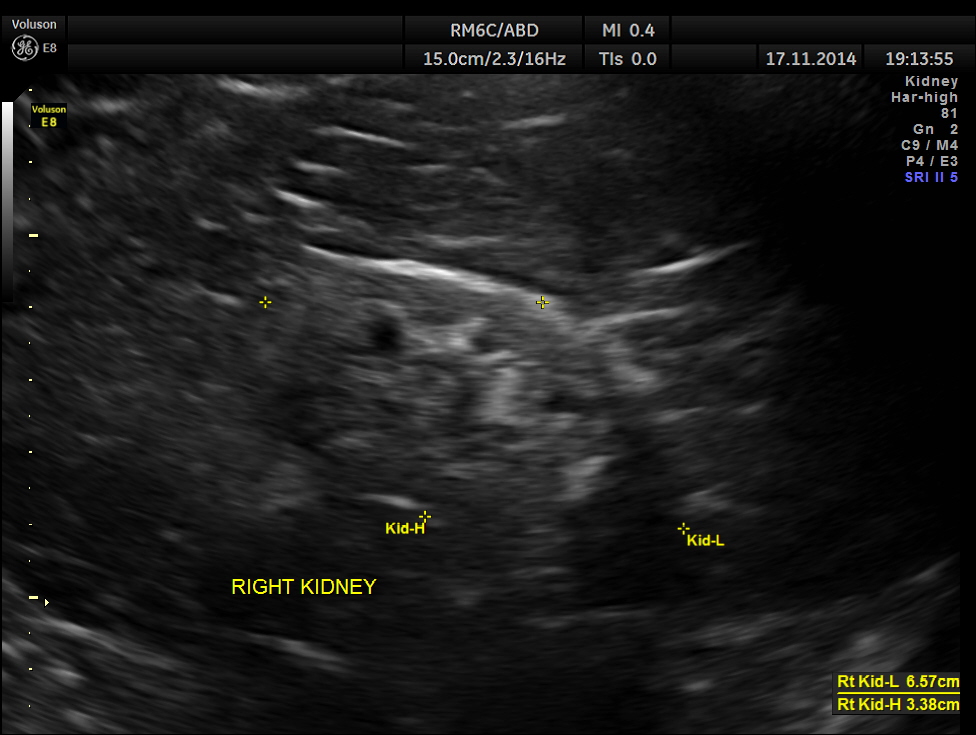

The following pictures show the native kidneys – shrunk with loss of renal architecture , with poor flow seen in Power Doppler.